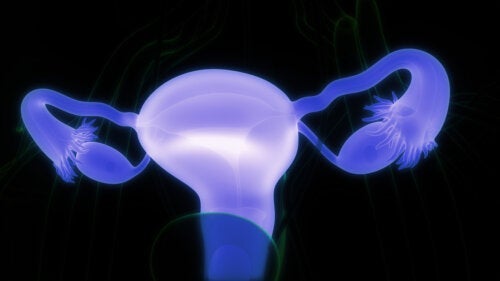

난소 유피낭종 증상, 진단 및 치료

난소 유피낭종은 임신부에게 가장 흔히 나타나는 질환이지만 조기 치료로 다른 합병증을 예방할 수 있다.

유피낭종은 모발, 치아, 체액 및 선 조직을 포함하는 주머니의 성장이다. 두개골, 척수, 얼굴 및 난소에서 형성될 수 있는 난소 유피낭종 증상, 진단 및 치료에 관해 알아보자.

난소 유피낭종은 출생 전에 형성되어 천천히 자라며 대개 양성이다. 조직학적 특징 때문에 성숙한 낭포성 기형종이라고도 하며 월경 주기와 관련된 호르몬 변화에 반응하지 않는다.